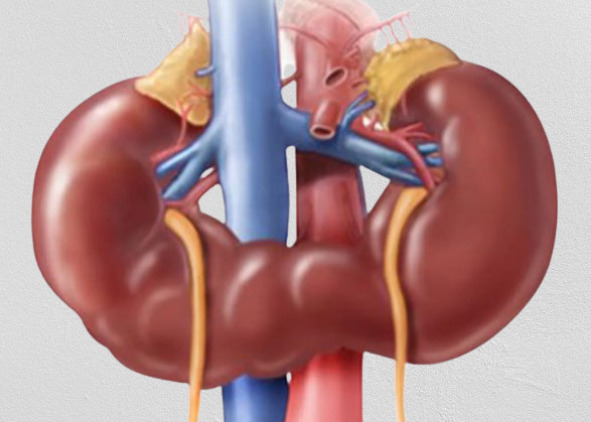

(Слева) Подковообразная почка. Нижние полюсы почек медиально отклонены, по срединной линии - перешеек. Питающие артерии, как правило, отходят от аорты или подвздошных артерий.

(Справа) Переднемедиальная ориентация лоханок может указывать на подковообразную почку. Тщательное сканирование по срединной линии позволяет даже во II триместре кпереди от аорты обнаружить паренхиматозную перемычку между почками.

о Чаще всего срастаются нижние полюсы почек:

- Перешеек лежит кпереди от аорты

- «Цепляется» за нижнюю брыжеечную артерию в процессе «восхождения»:

Как следствие - почки расположены ниже обычного

о Мочеточник впадает в лоханку выше и латеральнее нормы: